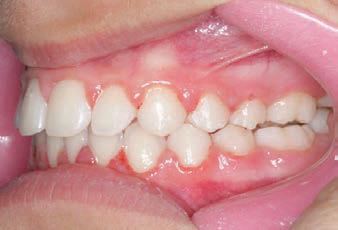

The SAGITTAL FIRST™ Philosophy is a time-tested approach that standardises, simplifies, and shortens Class II and Class III treatment times. It employs the Carriere Motion 3D Appliance to treat the AP dimension at the beginning of treatment before placing brackets or aligners. By resolving the most difficult part of treatment first, you can achieve a Class I platform in 3 to 6 months, shortening total treatment time by a minimum of 6 months1. You know how excited patients and parents become when you mention shorter treatment times.

CLASS II DIV.1 - Marra

INITIAL - 4/4/18

PROGRESS 1 - 26/9/18 - Class I platform accomplished in 5.75 months with Motion 3D COLOR Appliance

PROGRESS 2 - 26/9/18 - Placement of the SLX 3D Clear Brackets

with M-ONE .015 Cu Nitanium 27°

PROGRESS 3 - 30/10/18 - With M-TWO .020 x .020 Cu Nitanium 35° archwire

PROGRESS 4 - 27/11/18 - 3 links power chain: 5, 4, bypass 3 to crimp hooks

PROGRESS 5 - 13/3/19 - With M-TWO .020 x .020 Cu Nitanium 35° archwire

PROGRESS 6 - 1/8/19 - With M-THREE.019 x .025 Beta Titanium wire